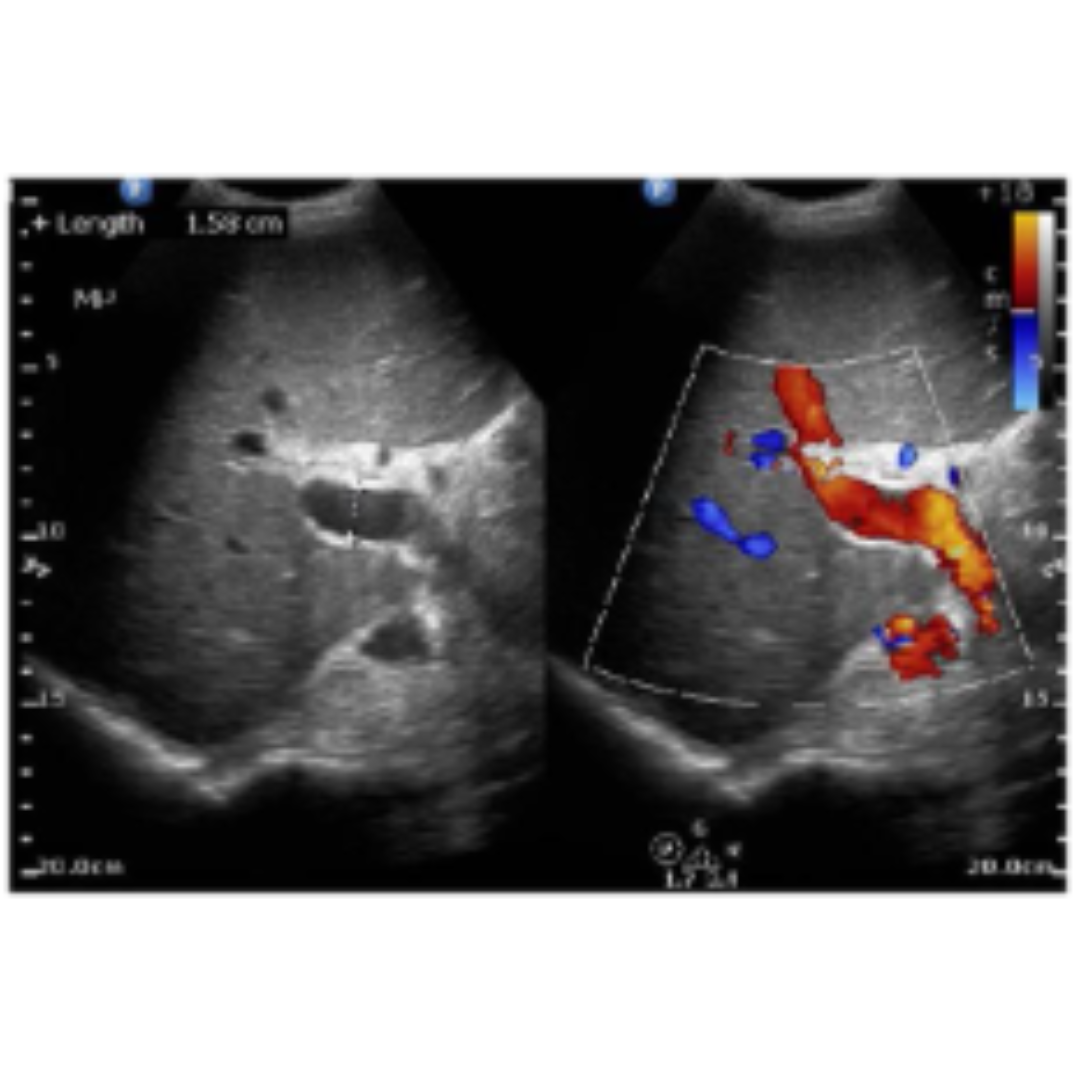

Daño Hepático Crónico: Hallazgos Ecográficos Importantes en Hepatopatía Crónica Parte II

Daño Hepático Crónico: Hallazgos Ecográficos Importantes en Hepatopatía Crónica Parte I